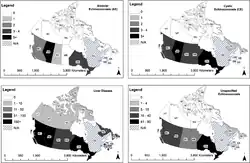

Epidemiology

The incidence of human infestation with E. multilocularis and disease is increasing in urban areas, as wild foxes (an important reservoir species of the sylvatic cycle) are migrating to urban and suburban areas and gaining closer contact with human populations.[4] Also, restocking fox enclosures for fox hunting with infected animals spreads the disease.[14] Children, health care workers and domestic animals are at risk of ingesting the eggs after coming into contact with the feces of infected wild foxes. Even with the improvement of health in developed/industrialized countries, the prevalence of alveolar echinococcosis (AE) did not decrease.[4] On the contrary, incidents of AE have now also been registered in eastern European countries and sporadic incidences in other European countries.[4]

The disease has extended its range in Europe in the last few decades.[15] Still the infection is fairly rare. Between 1982 and 2000 a total of 559 cases were reported throughout Europe.[16]

Recent findings indicate that E. multilocularis is likely expanding its range in the central region of the United States and Canada and that invasions of European strains might have occurred; the endemic presence of the parasite in urban areas and a total of 16 human cases in Alberta, Canada have been reported.[13][17] The first human case in Alberta was diagnosed in 2013. In one case, the infection caused a grapefruit sized tumour in the lung, kidney and diaphragm, which had to be surgically removed.[17] Because of the significant difficulty in diagnosising an infection caused by Echinococcus multiocularis, it is suspected that this parasite is often misdiagnosed. Several studies that have been done since the 1950s in North America indicate a higher prevalence of Echinococcus multiocularis than previously thought. However, due to limited knowledge about the parasite, it is often not monitored in wild or domestic animals; this monitoring will become crucial to the control of the parasite in the future as it continues to spread.[13]